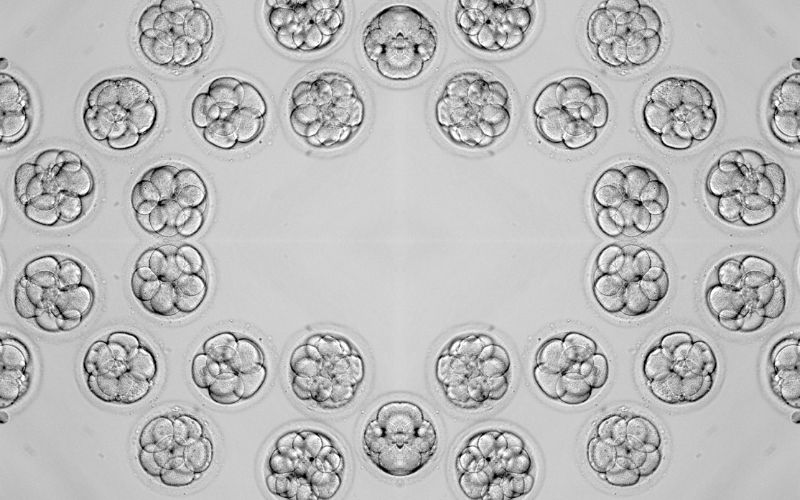

La clasificación embrionaria, distinguiendo entre los tipos A, B, C y D, es fundamental en los tratamientos de reproducción asistida. Establecer una diferenciación sirve para conocer la calidad y el potencial de cada embrión para desarrollarse tras la transferencia al útero, pero también orienta a los especialistas de las clínicas de fertilidad en su elección para aumentar las posibilidades de lograr un embarazo exitoso. La importancia de seleccionar los embriones de mejor calidad (Tipo A o B) radica en su mayor probabilidad de implantación, mientras que los tipos C y D presentan desafíos adicionales.